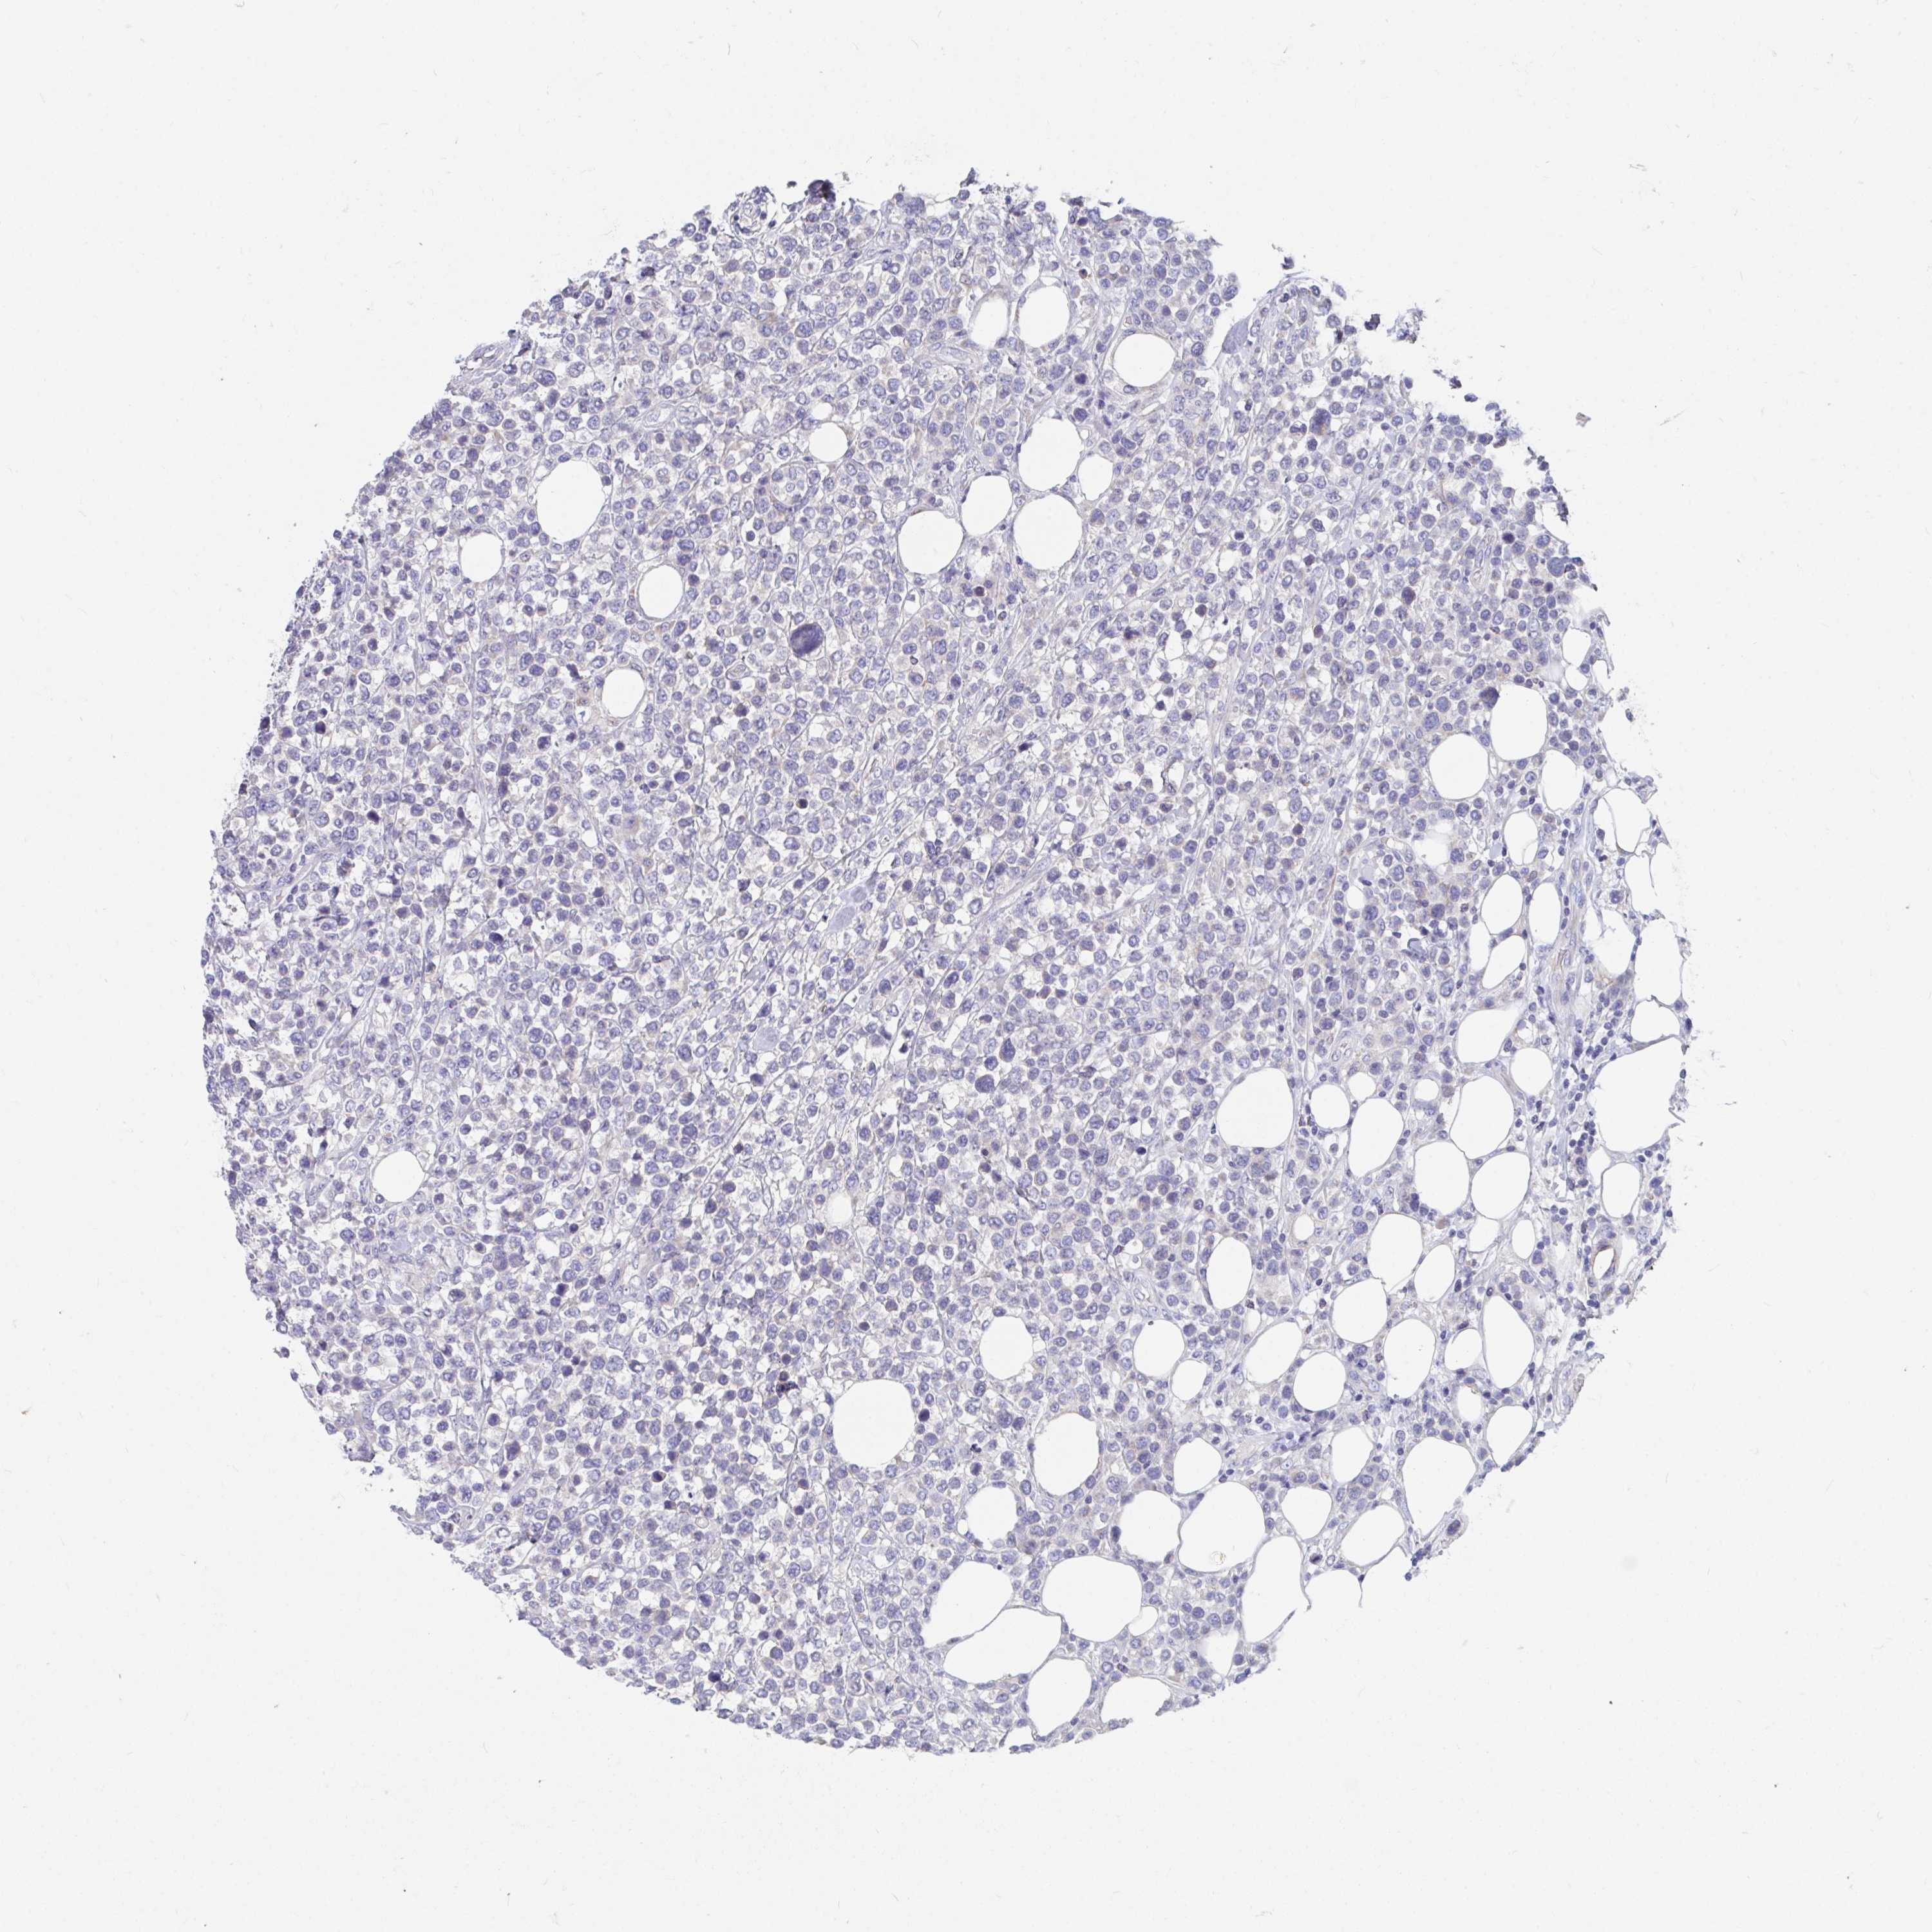

CANCER LYMPHOMA Show tissue menu

LYMPHOMA - Protein expressioni

A mouse-over function shows sample information and annotation data. Click on an image to view it in a full screen mode. Samples can be filtered based on level of antibody staining by selecting one or several of the following categories: high, medium, low and not detected. The assay and annotation is described here.

Each image is clickable and will lead to virtual microscopy that enables deeper exploration of all samples and also displays staining intensity scores, fraction scores and subcellular localization as well as patient and tissue information for each sample.

Antibody HPA055332

Malignant lymphoma, non-Hodgkin's type, Low grade

Malignant lymphoma, non-Hodgkin's type, High grade

Hodgkin's disease, NOS